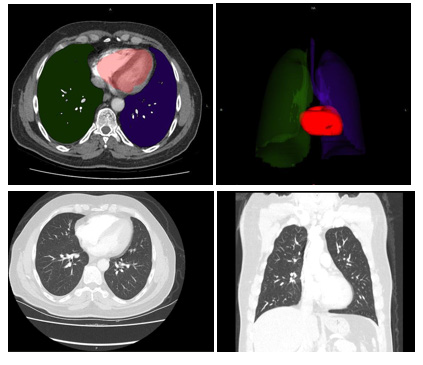

CCT scans were obtained from hospital’s automation system. A multi-slice computed tomography scanner (TOSHIBA Alexion 16 slice) was used for CCT imaging in the emergency service. CCT images on the hospital automation system were transferred to the Intrasense Myrian® (Myrian; Intrasense, Montpellier, France) software and 3D models of the data were recreated. Anatomical features of patients were defined on this application. Cardiac sections were colored to form 3D images and Total Cardiac Volume (TCV) were measured afterwards, which were carried out by an academic of anatomy. The resulting data were recorded on the data collection form (Figures 1&2).

Figure 1: A 55-year-old male patient was admitted to the emergency department with complaints of cough and fever. The patient’s reverse transcriptase polymerase chain reaction (PCR) test was positive. He was hospitalized in the intensive care unit with the diagnosis of COVID-19 pneumonia. Total heart volume measured using Intrasense Myrian® software was calculated as 460cm3 (Group 1).